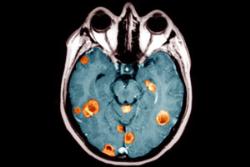

درمان سرطان مغز با سلول های چربی

دانشمندان دانشگاه جان هاپکینز در مطالعات آزمایشگاهی خود دریافتند سلول های بنیادی سلول های چربی بدن بیمار می تواند شیوه نوینی برای درمان مستقیم سرطان مغز پس از برداشتن تومور باشد.

محققان دانشگاه جان هاپکینز می گویند بزرگ ترین چالش در سرطان مغز، مهاجرت سلول های سرطانی است. حتی وقتی که جراح تومور را از مغز خارج می کند برخی از سلول های سرطانی به بخش های دیگری از مغز نفوذ کرده و در جای دیگری از این عضو دردسر ساز می شوند. سرطان گلیوبلاستوم رایج ترین و تهاجمی ترین نوع سرطان مغز است.

در حالی حاضر شیمی درمانی، پرتو درمانی و جراحی شیوه های رایج درمان سرطان مغز گلیوبلاستوم است اما حتی با استفاده از تمامی این شیوه ها، بیمار به ندرت می تواند بیش از 18 ماه پس از تشخیص بیماری اش زنده بماند.